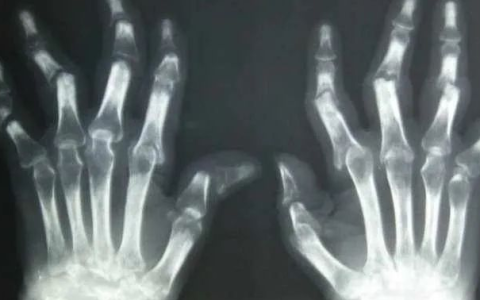

帕金森病(Parkinson’s disease, PD)是由英国医生詹姆斯•帕金森(James Parkinson)在1817年一篇关于震颤性麻痹的文章中提出的,是世界上发病率仅次于阿尔兹海默症的第二常见慢性神经退行性疾病。主要影响中老年人,多在60岁以后发病。其症状表现为静止时手、头或嘴不自主地震颤,肌肉僵直、运动缓慢以及姿势平衡障碍等,导致生活不能自理。

帕金森症是因人脑可分泌多巴胺(dopamine)的神经元逐渐死亡而致。多巴胺负责神经信息传递,包括控制肌肉活动。随着多巴胺量降低,病患脑功能开始退化,反应变得迟钝、动作缓慢,接着肢体不受控抖动。